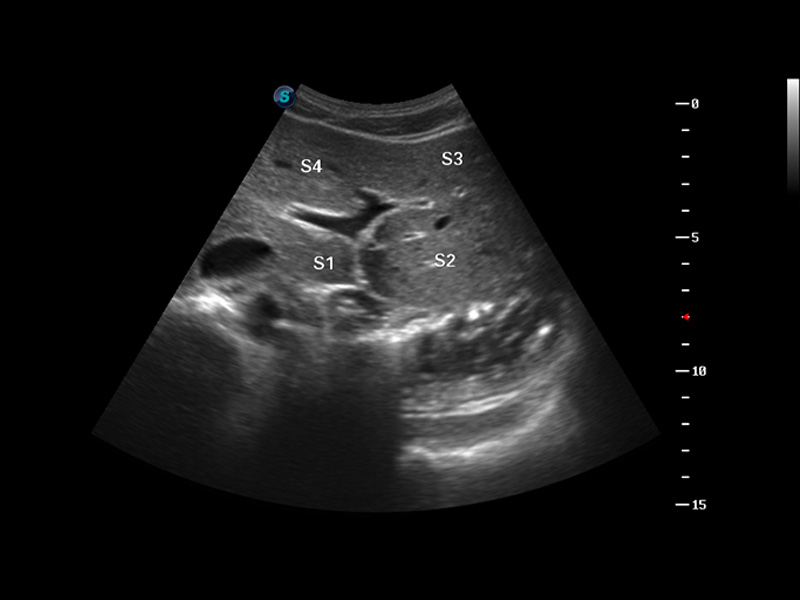

S8 EXP便攜式彩色多普勒超聲診斷儀是開立醫(yī)療研發(fā)的高端全身應(yīng)用型便攜彩超。高通道的VIS平臺(tái)融合可視化(Visual)、智能化(Intelligent)和人性化(Smart)的特點(diǎn),配以開立醫(yī)療自主研發(fā)生產(chǎn)的探頭大家族,使您能夠快速、準(zhǔn)確的獲得病人信息,提高工作效率的同時(shí)減輕疲勞。

實(shí)時(shí)寬景成像

3D/4D成像